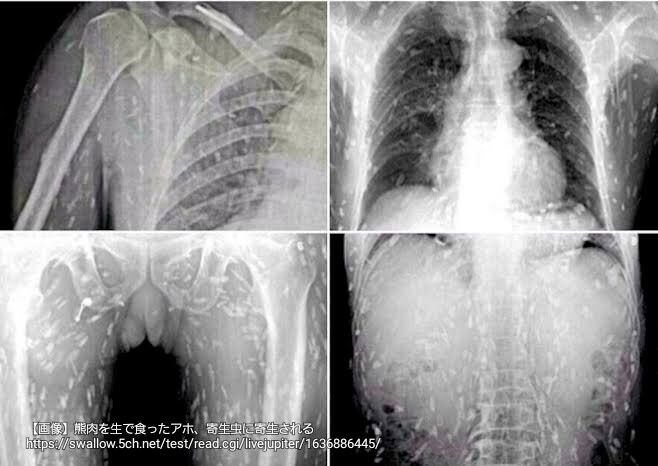

画像ファイル名:1763885848435.jpg-(42557 B)

42557 B無念Nameとしあき25/11/23(日)17:17:28No.1368186001そうだねx4 21:51頃消えます

熊怖い

中国人女性が有鈎条虫に寄生されたレントゲン写真に似て居るな

1763887696139.jpg-(35999 B)

>中国人女性が有鈎条虫に寄生されたレントゲン写真に似て居るな

それはコチラ

1763894855522.png-(357552 B)

>2ちゃんからパクってきたんか

画像は2ちゃん以外だな

https://www.dailymail.co.uk/health/article-2768117/Sushi-lover-s-entire-body-left-riddled-tapeworm-parasites-eating-contaminated-sashimi.html [link]